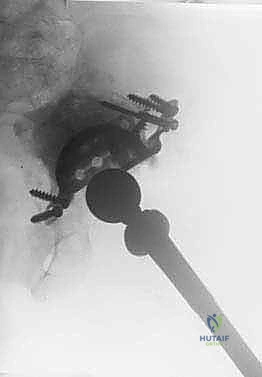

- الأشعة السينية (X-rays): صور متعددة الزوايا للحوض ومفصل الورك لتقييم وضع المفصل القديم، ومقدار هجرته، وعلامات تحلل العظم.

- الأشعة المقطعية ثلاثية الأبعاد (3D CT Scan): هذا هو الفحص الأهم على الإطلاق للتخطيط لجراحة القفص. يوفر صورة مجسمة دقيقة توضح حجم العيب العظمي، ومكان العظم السليم المتبقي الذي سيتم تثبيت مسامير القفص فيه.

1. الشفة العلوية (Iliac Flange): تمتد لأعلى لتُثبت بمسامير قوية في عظم الحرقفة (Ilium) الصلب.

2. الشفة السفلية (Ischial Flange): تمتد لأسفل لتُغرس أو تُثبت في عظم الورك (Ischium).

بهذه الطريقة، عندما يقف المريض، لا ينتقل وزنه إلى العظم الضعيف المحطم، بل ينتقل عبر هيكل القفص المعدني الصلب إلى العظام السليمة في الأعلى والأسفل. هذا يحمي الترقيع العظمي (الذي يتم وضعه تحت القفص) من الضغط المفرط، مما يسمح له بالالتئام والتحول إلى عظم حي قوي بمرور الوقت. بمجرد تثبيت القفص بقوة، يتم تثبيت كوب بلاستيكي (Polyethylene Cup) داخله باستخدام الأسمنت الطبي، ليتمفصل مع رأس عظم الفخذ الجديد.